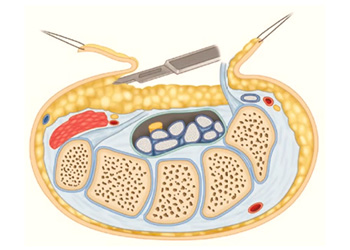

OVT video shows hypothenar fat pad flap is a reliable way to obtain local coverage of the median

Carpal tunnel syndrome is one of the most prevalent focal mononeuropathies, constituting 90% of neuropathy cases.